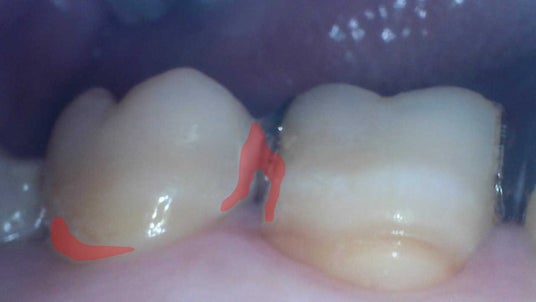

画像認識AIが認識した汚れ付着部位を赤く示した画像

「口腔ケアサポート技術」では、専用口腔内カメラを使用して自身で撮影した口腔内画像を画像認識AIサーバーへ送信すると、画像認識AIが汚れ付着箇所を認識し着色を行います。

発見した汚れ部位を赤く示した画像

なお本活動では、口腔内画像を1000枚以上収集して画像認識AIを構築し、本AIによる汚れ発見の精度はIoU0.421(※3)です。